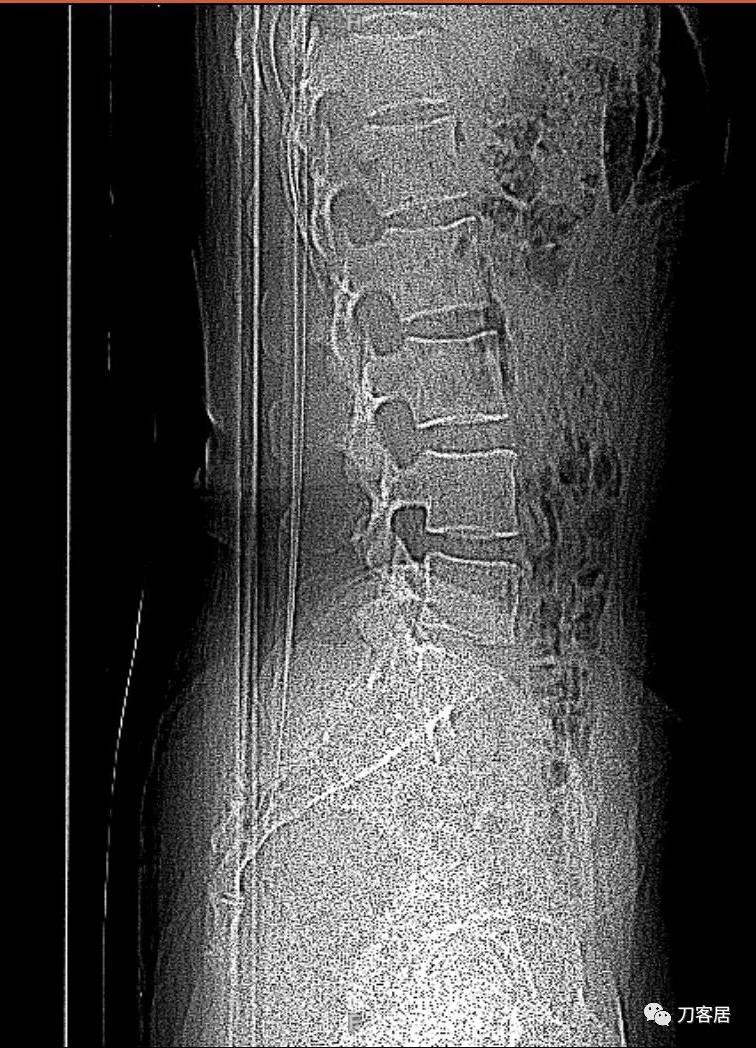

图1. 微创术前腰椎MRI矢状面T2相,提示腰5骶1椎间盘突出,腰4-骶1椎体对应平面后方软组织结构紊乱,应该是以前做过手术。

图2. 微创术前腰椎MRI矢状面T2相,提示腰5骶1椎间盘突出,腰5-骶1椎管内后方软组织结构紊乱,应该是以前做过手术。

图5. 微创术前腰椎CT定位片,因为没有获取到患者的腰椎正侧位X线片,所以,用此片判断腰椎无峡部裂,无滑脱,无移位,无骨折等。